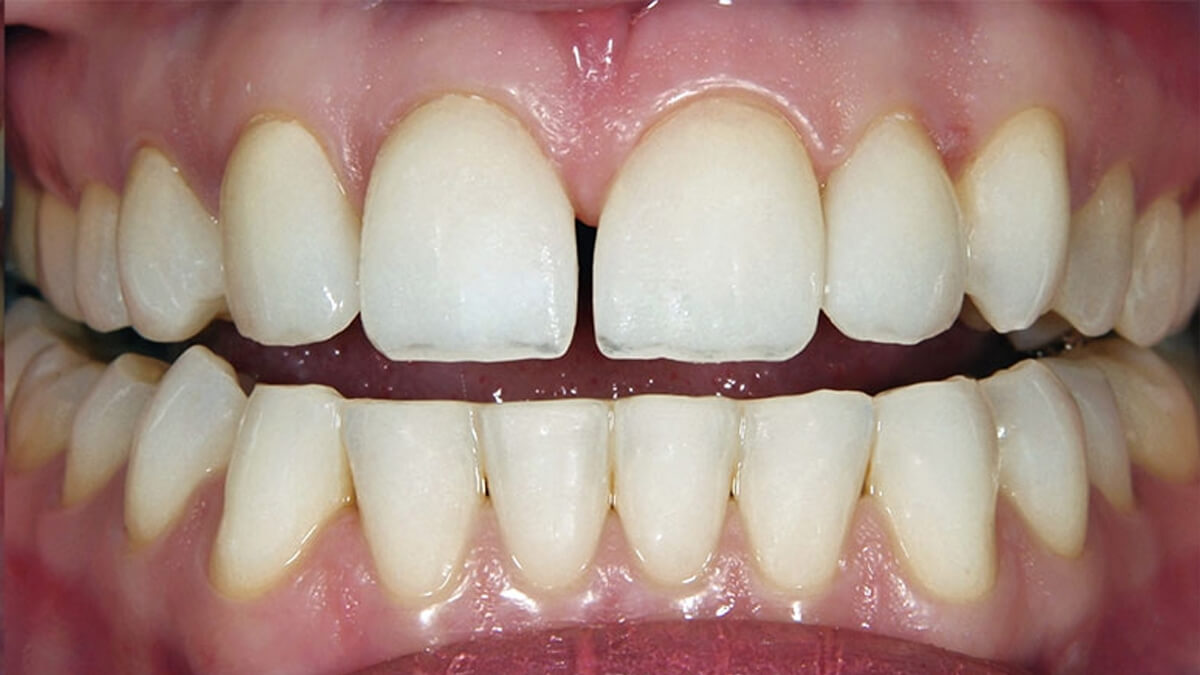

Általában ha a fognak csak egy kisebb része szuvas, a hiányzó rész kitisztítás után tömőanyaggal pótolható. A töméskészítést helyi érzéstelenítésben végezzük, egy alkalmat vesz igénybe. A tömőanyag egy speciális műanyag, kompozit, amely mind színében, mind fizikai tulajdonságaiban nagymértékben hasonlít a természetes foghoz, ezért alkalmas tartós és esztétikus tömések készítésére. Töméskészítés során a gyurmaszerű anyagot kis adagokban helyezzük az üregbe, majd az egyes rétegeket speciális lámpával világítjuk meg, melynek hatására megszilárdulnak. A tömés elkészültével az anyag kötése befejeződik, a fog terhelhető.

A tömőanyag tulajdonságaiból adódóan ma már, ha az üreg nem túl nagy, minden fogcsoport tömésére alkalmazható. Rágófogakban képes helyreállítani a funkciót, azaz egy erős, a rágóerőkkel szemben ellenálló tömés készíthető, frontfogakba (metszőfogak) pedig készülhet olyan esztétikus, észrevehetetlen tömés, mely kedvezően befolyásolhatja megjelenésünket, arckarakterünket.